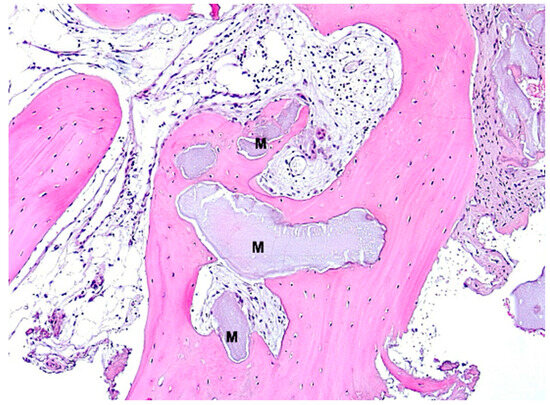

3. Results